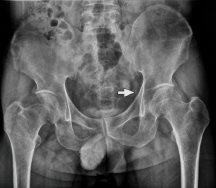

Planos de Rx para pinzamiento femoroacetabular

- AP y oblicua - Axial (Dunn)

44

Imagen que permite mejor evaluación anatómica | Pinzamiento femoroacetabular

TC | Reconstrucción 3D

45

Mejor método de imagen para pinzamiento femoroacetabular

RM

46

¿Qué se ve en la RM? | Pinzamiento femoroacetabular

- Permite ver edema óseo - Pinzamiento leve - Quistes - Lesión Labrum